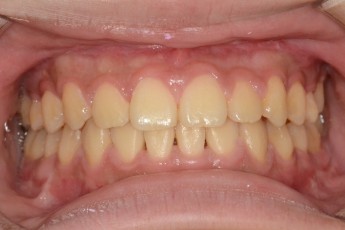

Before

After